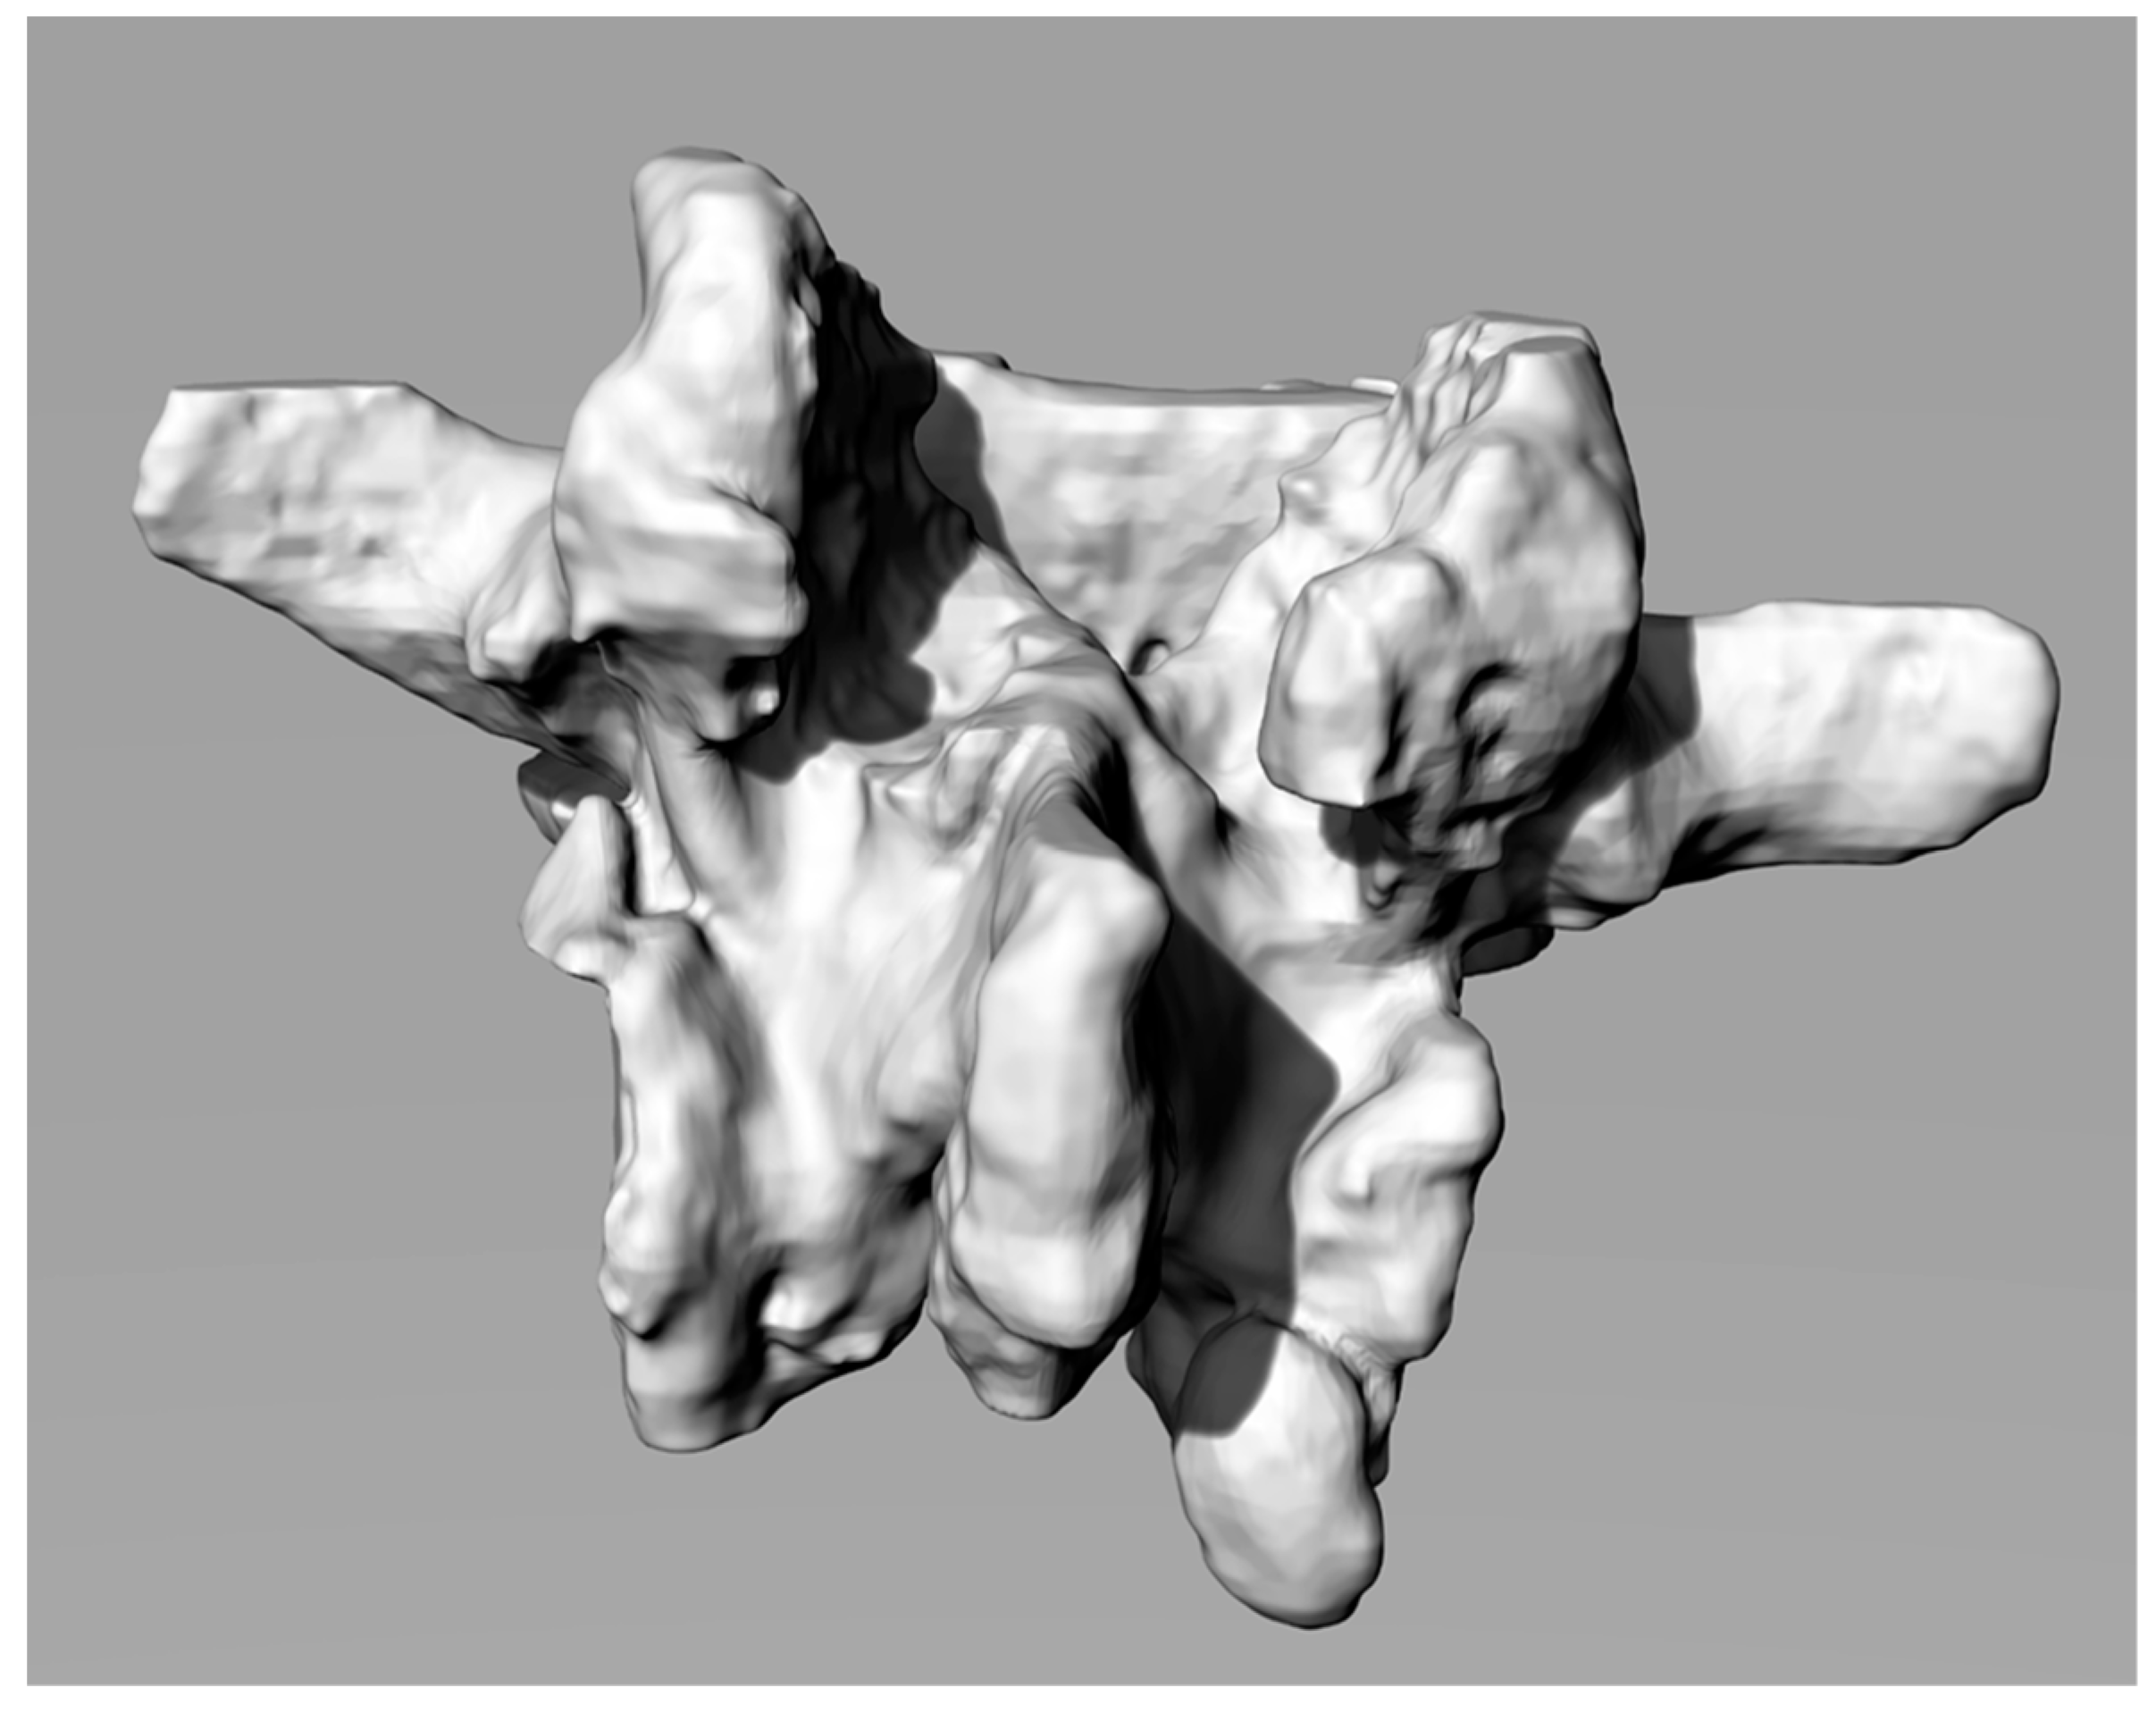

Segmentation generates 3D Standard-Triangulation-Language (STL) models of the vertebrae that were imported into Geomagic software (3D Systems— Rock Hill (SC), USA) for conversions in poli-surfaces format (IGES). This step is particularly useful because the IGES model is composed by closed surfaces that are suitable for processing with CAD modelling software. After the conversion into IGES format, the vertebral model was imported using the Rhinoceros Software (Robert McNeel & Associates—Seattle, WA, USA). Figure 1 shows a 3D reconstruction.

Therefore, it is appropriate to cut the 3D model of the template in its internal surfaces so as not to generate interference and under-cuts with the surfaces of the spinous process. On the solid, tubes and holes have to be created along the already verified trajectories for creating the guides for the screws. Figure 2 shows the final shape of the solid.

Figure 1. Computer-aided-design (CAD) reconstruction of a lumbar vertebra.